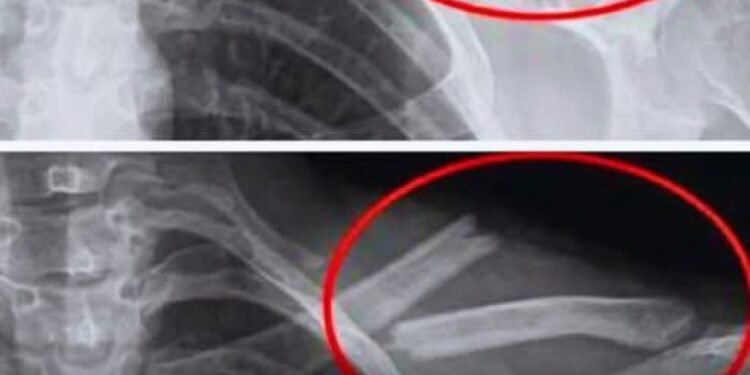

Studien zeigen, dass übermäßiger Limonadenkonsum mit einer Verringerung der Knochendichte einhergeht, insbesondere bei Frauen. Mit anderen Worten: Ihre Knochen werden brüchiger … manchmal ohne jegliche Symptome, bis es zu einem Bruch kommt.

Eine US-Studie mit 2.500 Frauen ergab, dass diejenigen, die regelmäßig Cola konsumierten, eine geringere Knochendichte in den Hüften hatten. Und dies, ohne dass man sich dessen bewusst ist.